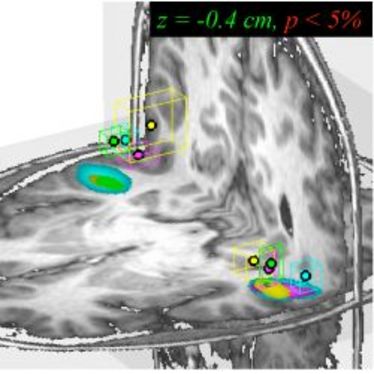

1. Small Animal Imaging Workshop in Münster

1. Small Animal Imaging Workshop in Münster

22.11.2010

- 26.11.2010

1. Small Animal Imaging Workshop in Münster

1. Small Animal Imaging Workshop in Münster

22.11.2010

- 26.11.2010

1. Small Animal Imaging Workshop in Münster

1. Small Animal Imaging Workshop in Münster